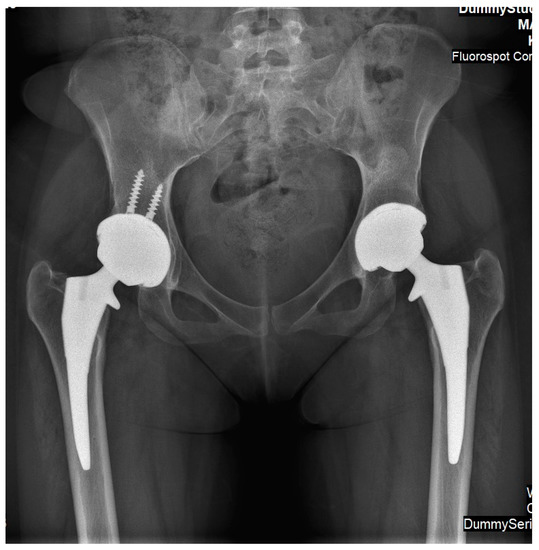

HOT ! 大腿骨近位部骨折 Osteosynthesis & Arthroplasty Frontiers | Multiple osteofibrous dysplasia combined with

大腿骨近位部骨折 Osteosynthesis & Arthroplasty Frontiers | Multiple osteofibrous dysplasia combined withの詳細情報

Frontiers | Multiple osteofibrous dysplasia combined with。JBJS: Triple Pelvic Osteotomy Provides Joint Stability and。Treatment of total hip arthroplasty between two surgical。大腿骨近位部骨折の手術手技に関する専門書。- タイトル: 大腿骨近位部骨折 Osteosynthesis & Arthroplasty- 著者: 高平尚伸, 鈴木恵美, 神田善男, 北田貴司- 内容: 大腿骨頚部・転子部・転子下骨折の手術手技に関する専門書- 出版社: メディカ出版- ISBN: 9784840451003ご覧いただきありがとうございます。裁断済みスキャン済みのためヨレや小傷はあります業者に裁断してもらいました書き込みはありません価格交渉やまとめ買いはご相談ください。Cross-Union Surgery for Congenital Pseudarthrosis of the Tibia。医学書 まとめ売り

• Frontiers | Multiple osteofibrous dysplasia combined with

• JBJS: Triple Pelvic Osteotomy Provides Joint Stability and

• Treatment of total hip arthroplasty between two surgical